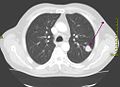

Der Unterschied zwischen der überlagerungsfreien Darstellung in der medizinischen Tomografie und einer Projektionsabbildung ist in den nachfolgenden Abbildungen illustriert. In Projektionsverfahren wie der Radiografie (gewöhnliche Röntgenuntersuchung) wird ein Schattenbild aufgenommen, auf dem sich mehrere Strukturen überlagern, wenn sie im Strahlengang hintereinander liegen. Beispielsweise überlagern beim konventionellen Röntgenbild die Weichteile der vorderen und hinteren Brustwand und die knöchernen Strukturen des Thorax die Lungenstrukturen. Dies würde die Diagnose eines Lungentumors (z. B. Bronchialkarzinom) erschweren. Jedes CT- oder MRT-Schnittbild vom Thorax zeigt dagegen nur eine 0,5 bis 10 mm dicke Schicht, die praktisch überlagerungsfrei ist.

Derselbe Tumor in der Computertomografie (axiales Schnittbild) -